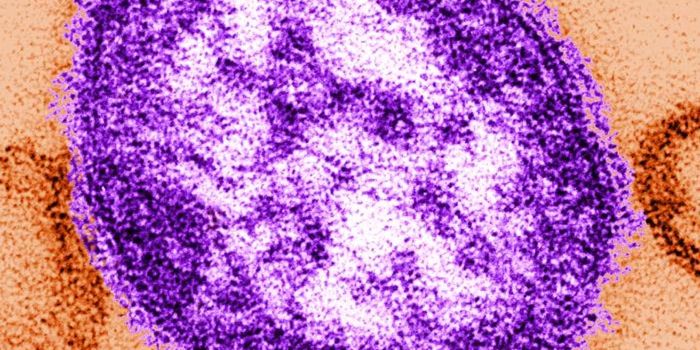

FEB 12, 2018ImmunologyThere is more to the measles vaccine than just protection from a measles infection, a new Frontiers study shows. A monum ...

SEP 07, 2018Health & MedicineMeasles is a disease that many believe was eradicated years ago. That's true, to a point, but like a bad penny, it&# ...

OCT 01, 2019InfographicsMeasles outbreaks continue to make news around the world. The Centers for Disease Control and Prevention update on a wee ...